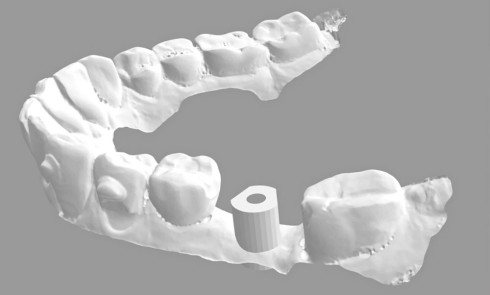

• Les empreintes secondaires anatomophysiologiques sont coulées. Les modèles obtenus doivent comporter toutes les morphologies et les limites données pour l’empreinte.

• Le modelage fonctionnel mandibulaire issu de la piézographie est transformé en maquette d’occlusion. Son volume est homothétique à celui du modelage.

• Les maquettes d’occlusion sont montées en articulateur et l’agencement des dents artificielles est abordé en accordant une priorité absolue au montage des dents mandibulaires, tenant compte des données fonctionnelles obtenues dans l’enregistrement des rapports intermaxillaires et de la piézographie.